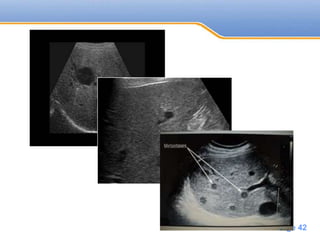

Ultrasound

Hypoechoic metastasis

• Lymphoma

• Sarcoma

• Most adenocarcinoma(breast, lung, pancreas)

• #42 Lung ca target appearance

• #43 Hypoechoic liver metastases of a colon carcinoma Hypoechoic liver metastases of a melanoma